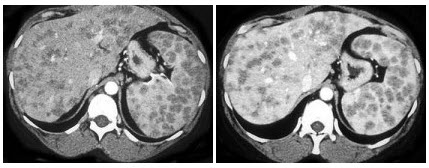

2、单项选择题

男,61岁,寒颤高热,右上腹痛,白细胞计数升高,CT检查如图,最可能的诊断是()

A.原发性肝癌

B.肝血管瘤

C.肝脓肿

D.炎性肉芽肿

E.肝转移癌